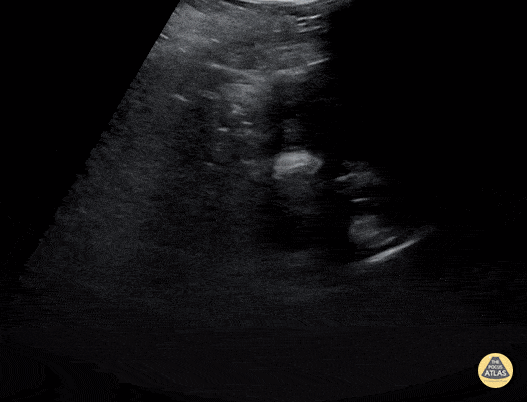

Renal & Bladder Pathology

Peds-Genitourinary